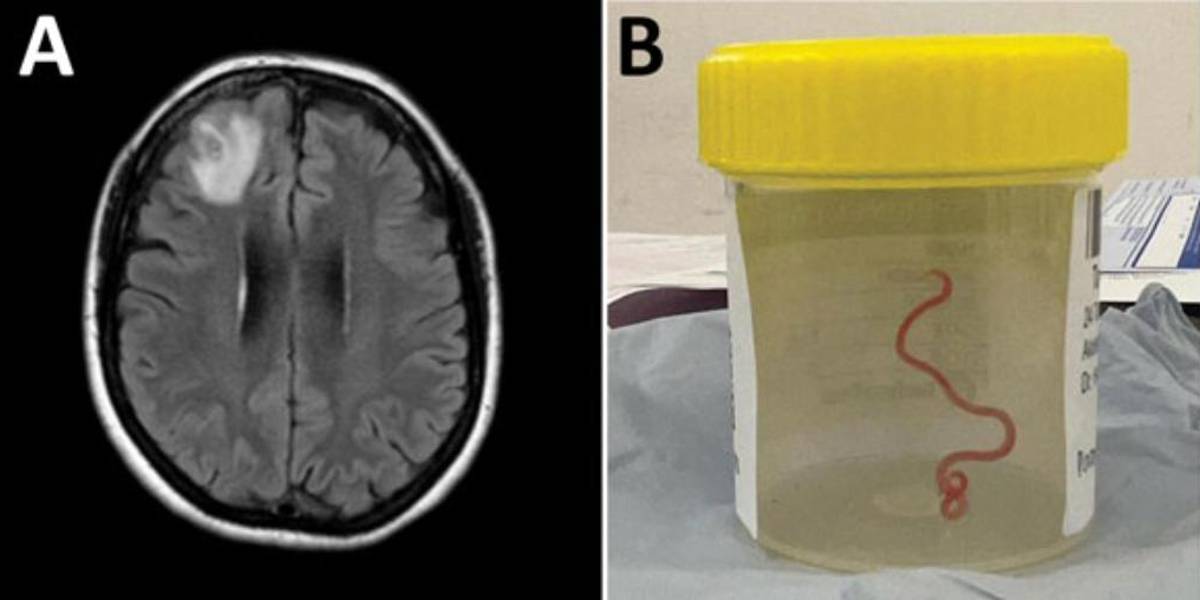

En 2022, la paciente se sometió a una resonancia magnética tras experimentar trastornos en la memoria y depresión. Las imágenes del cerebro de la paciente revelaron que la mujer tenía una lesión atípica en el lóbulo frontal derecho.

Un neurocirujano del Hospital de Canberra exploró la anomalía y fue entonces cuando se encontró la inesperada lombriz intestinal de ocho centímetros.

El parásito fue extraído, vivo y retorciéndose, de la paciente durante de una cirugía cerebral, de la que no se precisa la fecha, y actualmente la mujer continúa siendo examinada por el equipo de especialistas en enfermedades infecciosas y cerebro.